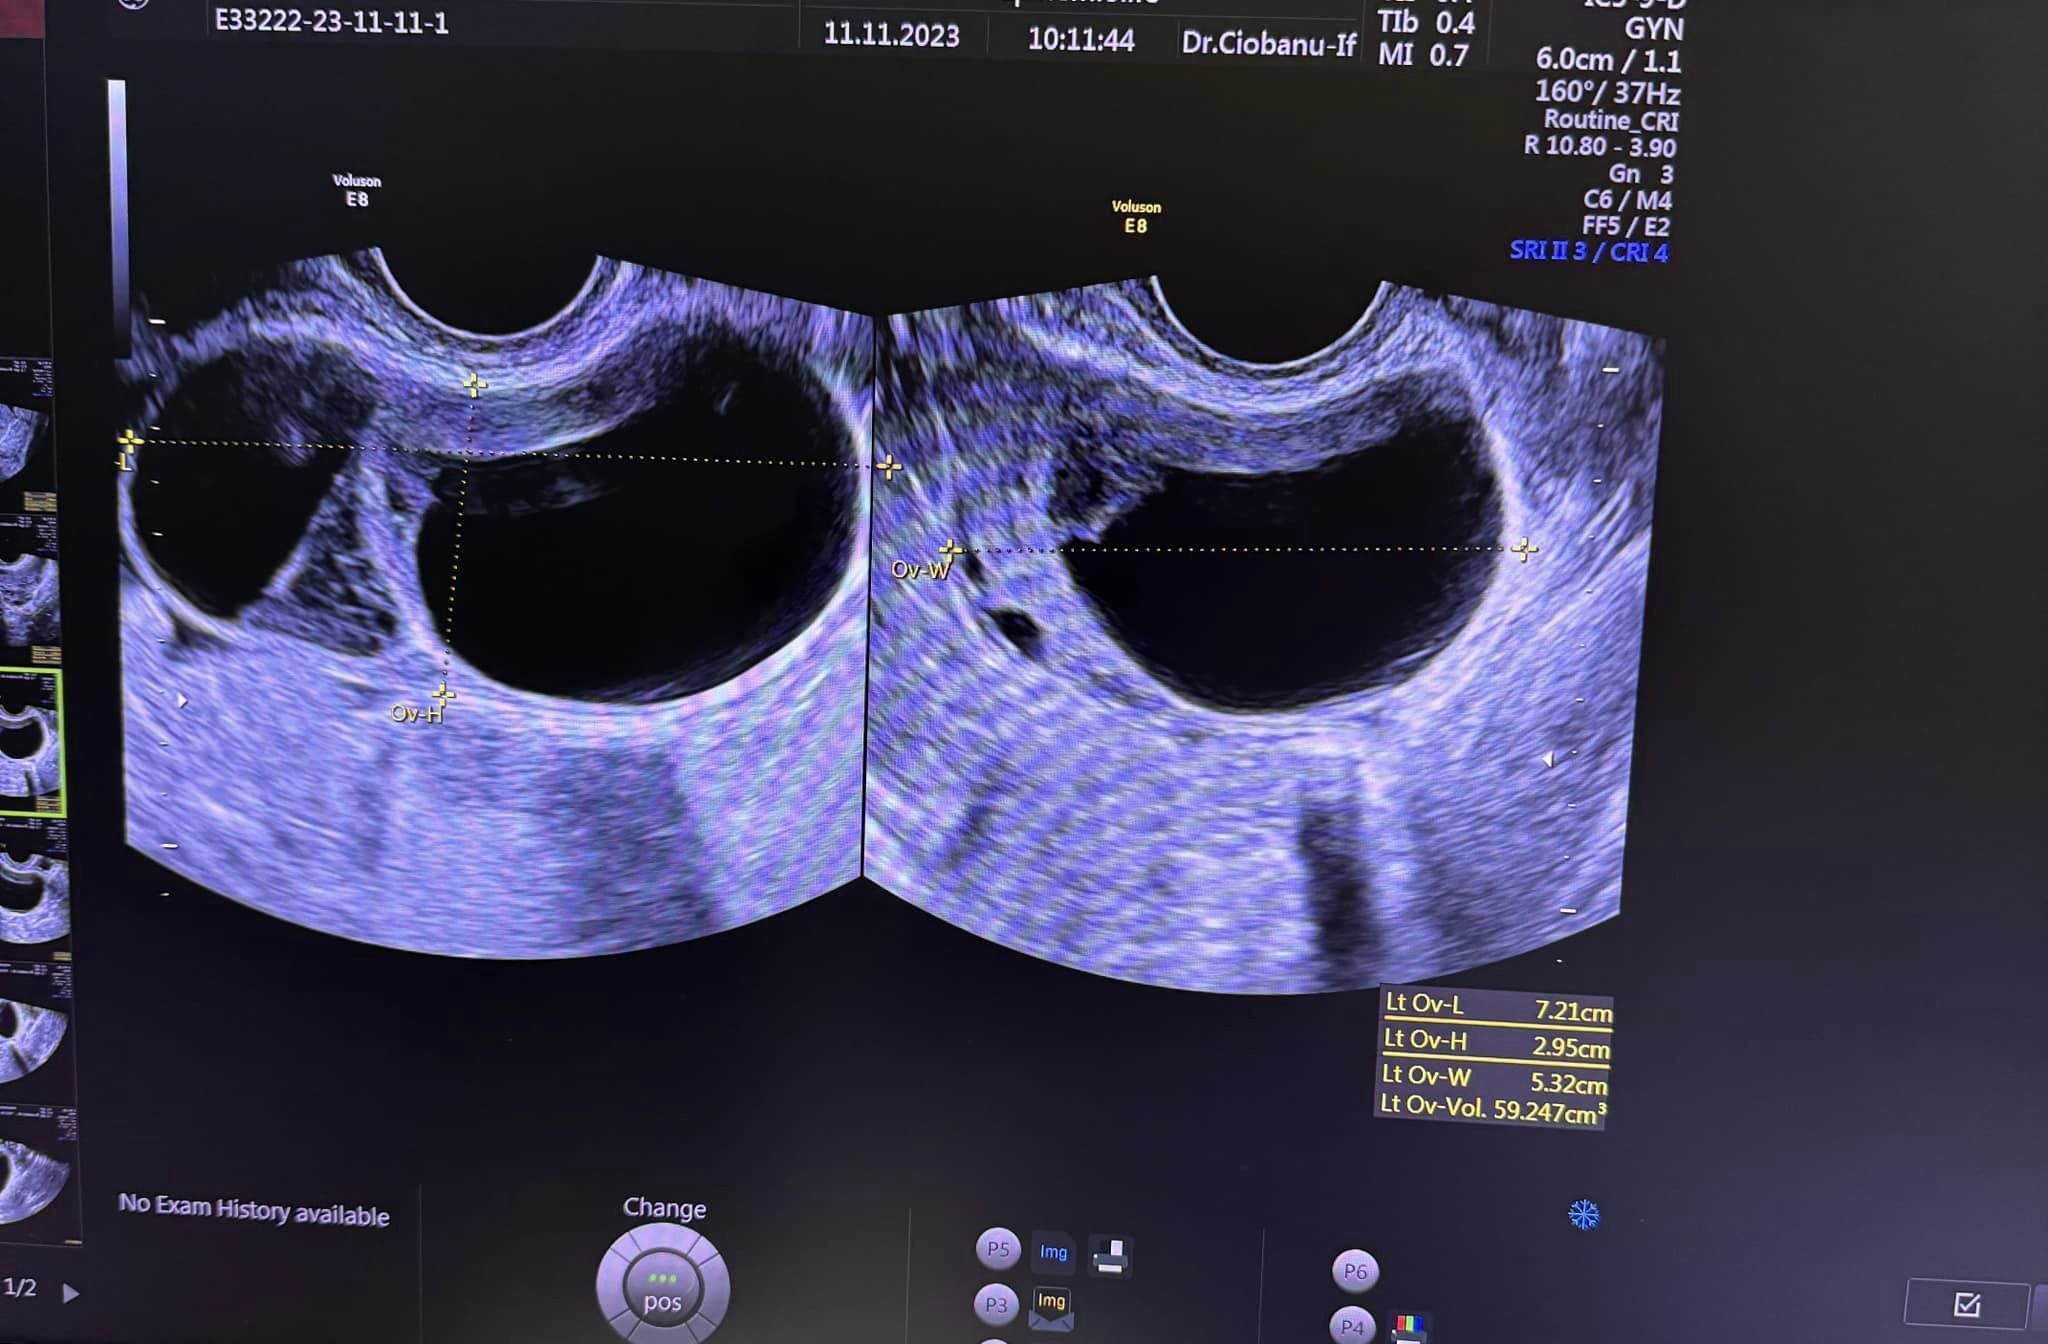

Pacientă în vârstă de 28 ani care s-a prezentat la medic pentru dereglări menstruale și dureri abdominale, și pe care am văzut-o prima dată în luna noiembrie, speriată fiind de diagnosticul primit și de faptul ca i s-a recomandat să se opereze pentru a scoate chistul, pe care am revăzut-o la control, după aproximativ 4 luni de tratament.